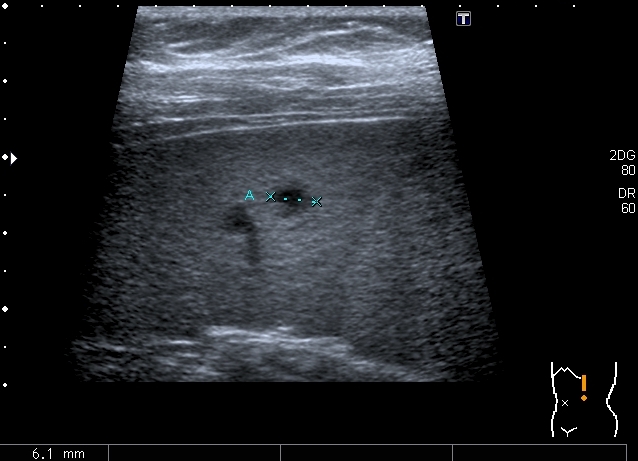

Девочка 13 лет, в течение 2-х недель температура до 38, СОЭ - 40 мм\ч, СРБ - 30.

На УЗИ: Учитывая клинику, лабораторные данные поставил гистиоцитарную инфильтрацию печени и селезёнки при генерализованной инфекции. Несколько раз встречался со схожими случаями, на фоне антибиотикотерапии изменения уходили. Но в данном случае девочка уже получала антибиотики в течение недели, на этом фоне не получено ни клинического , ни лабораторного улучшения, а на УЗИ очаги стали больше. Нужно ли расширять дифференциально -диагностический ряд? Ваши мнения

Имхо, по УЗ-семиотике - множественные небольшие абсцессы.

Из -за того , как назвать данные изменения у нас в больнице постоянно возникают споры между педиатрами и хирургами, а крайние - мы. Если мы в своём заключении упомянём слово "абсцесс" - девочку сразу же переведут в хирургическое отделение: абсцесс= гной, где гной - там разрез. Весь вопрос в том , что гноя в этих очагах нет и хирурги категорически отказываются участвовать в лечении данного заболевания, скорее это инфильтраты, или по лекции С. И. Пиманова - гистиоцитоз печени и селезёнки. Упомянув данное слово , мы ввергаем педиатров в панику, т. к. у них возникает ассоциация с гистиоцитозом X, хотя это несолько из другой оперы.KapustinSV писал(а):Имхо, по УЗ-семиотике - множественные небольшие абсцессы.

Мне нравится информация по данной патологии из видаровского "Клинического руководства по ультразвуковой диагностике в педатрии". Там данные изменения носят название очаговых поражений инфекционной этиологии (иерсиниоз, псевдотуберкулёз, токсокароз, хламидиоз и др.). Но инфекционисты, проведя ИФА с очень скудным набором диагностикумов и получив отрицательный результат, так же говорят, что это "не их".